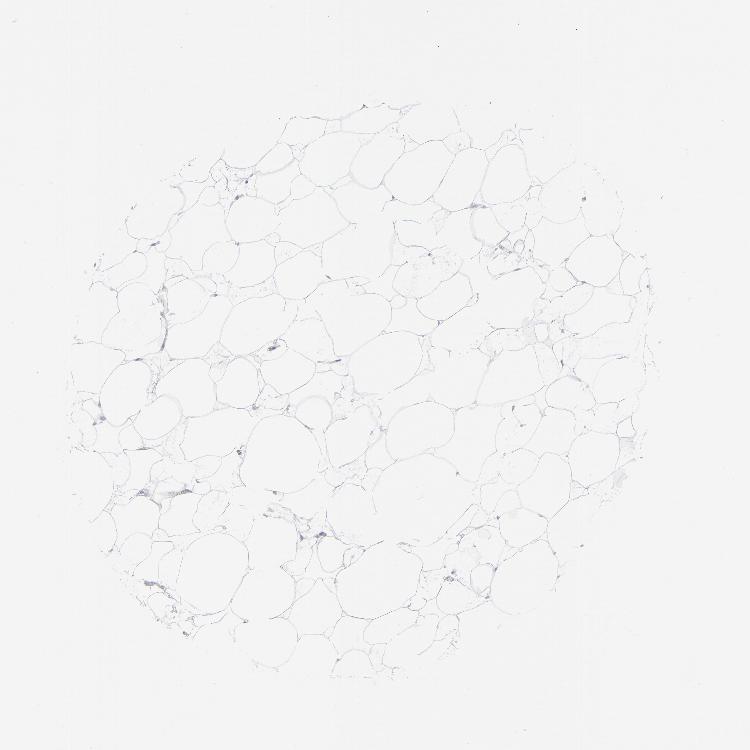

SOFT TISSUE 2 - Antibody stainingi

Antibody staining in the annotated cell types in the current human tissue is reported as not detected, low, medium, or high, based on conventional immunohistochemistry profiling in selected tissues. This score is based on the combination of the staining intensity and fraction of stained cells.

Each image is clickable and will lead to virtual microscopy that enables deeper exploration of all samples and also displays staining intensity scores, fraction scores and subcellular localization as well as patient and tissue information for each sample.

Antibody HPA017172Antibody CAB002216Antibody CAB080356

Fibroblasts Not detectedNot detectedMedium

Peripheral nerve Not detectedNot detectedNot detected